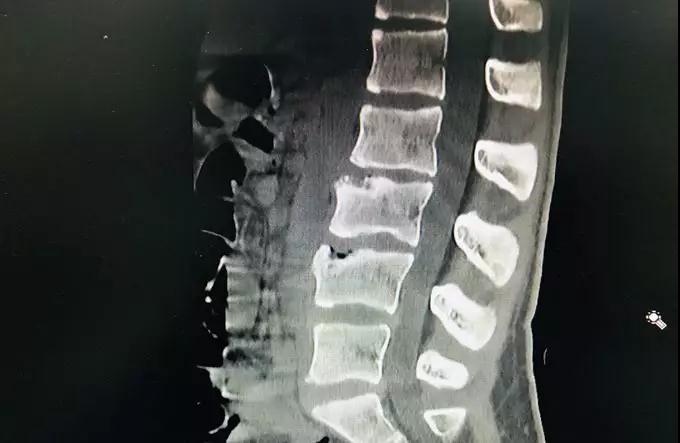

CT及MR检查

影像学上,发现部分椎体的前缘已经出现了楔形改变,且椎体出现了骨质疏松、分节、局部密度增高等表现,椎体形态不规则,正常骺板与椎体间的透明线不规则增宽。经过深圳市中医院骨伤科曹亚飞主任、李亨博士诊治后,确诊为休门氏病,经治疗后小琪的症状已经明显的缓解,又可以挺胸抬头的去上学了。